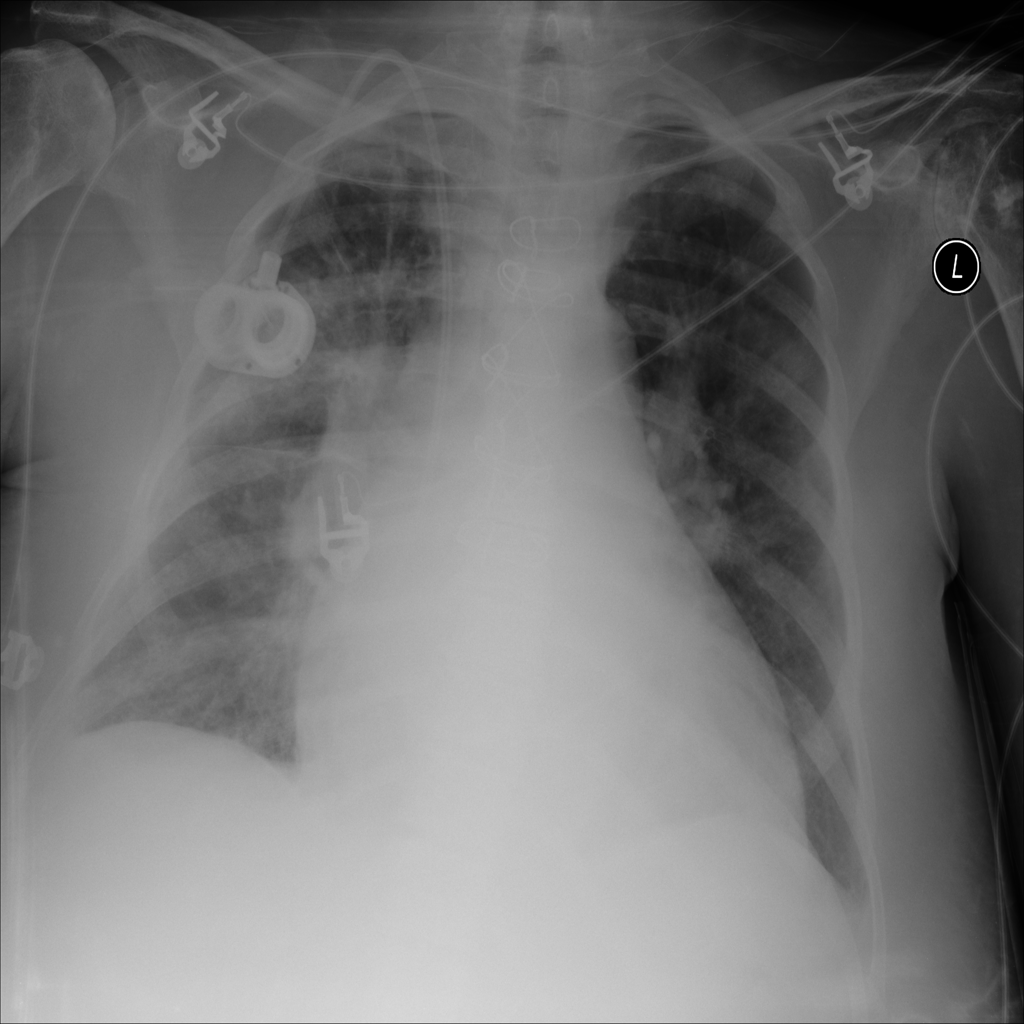

PAT-F3E7 · IMG-000Cardiomegaly

PAT-F3E7 · IMG-000

PA